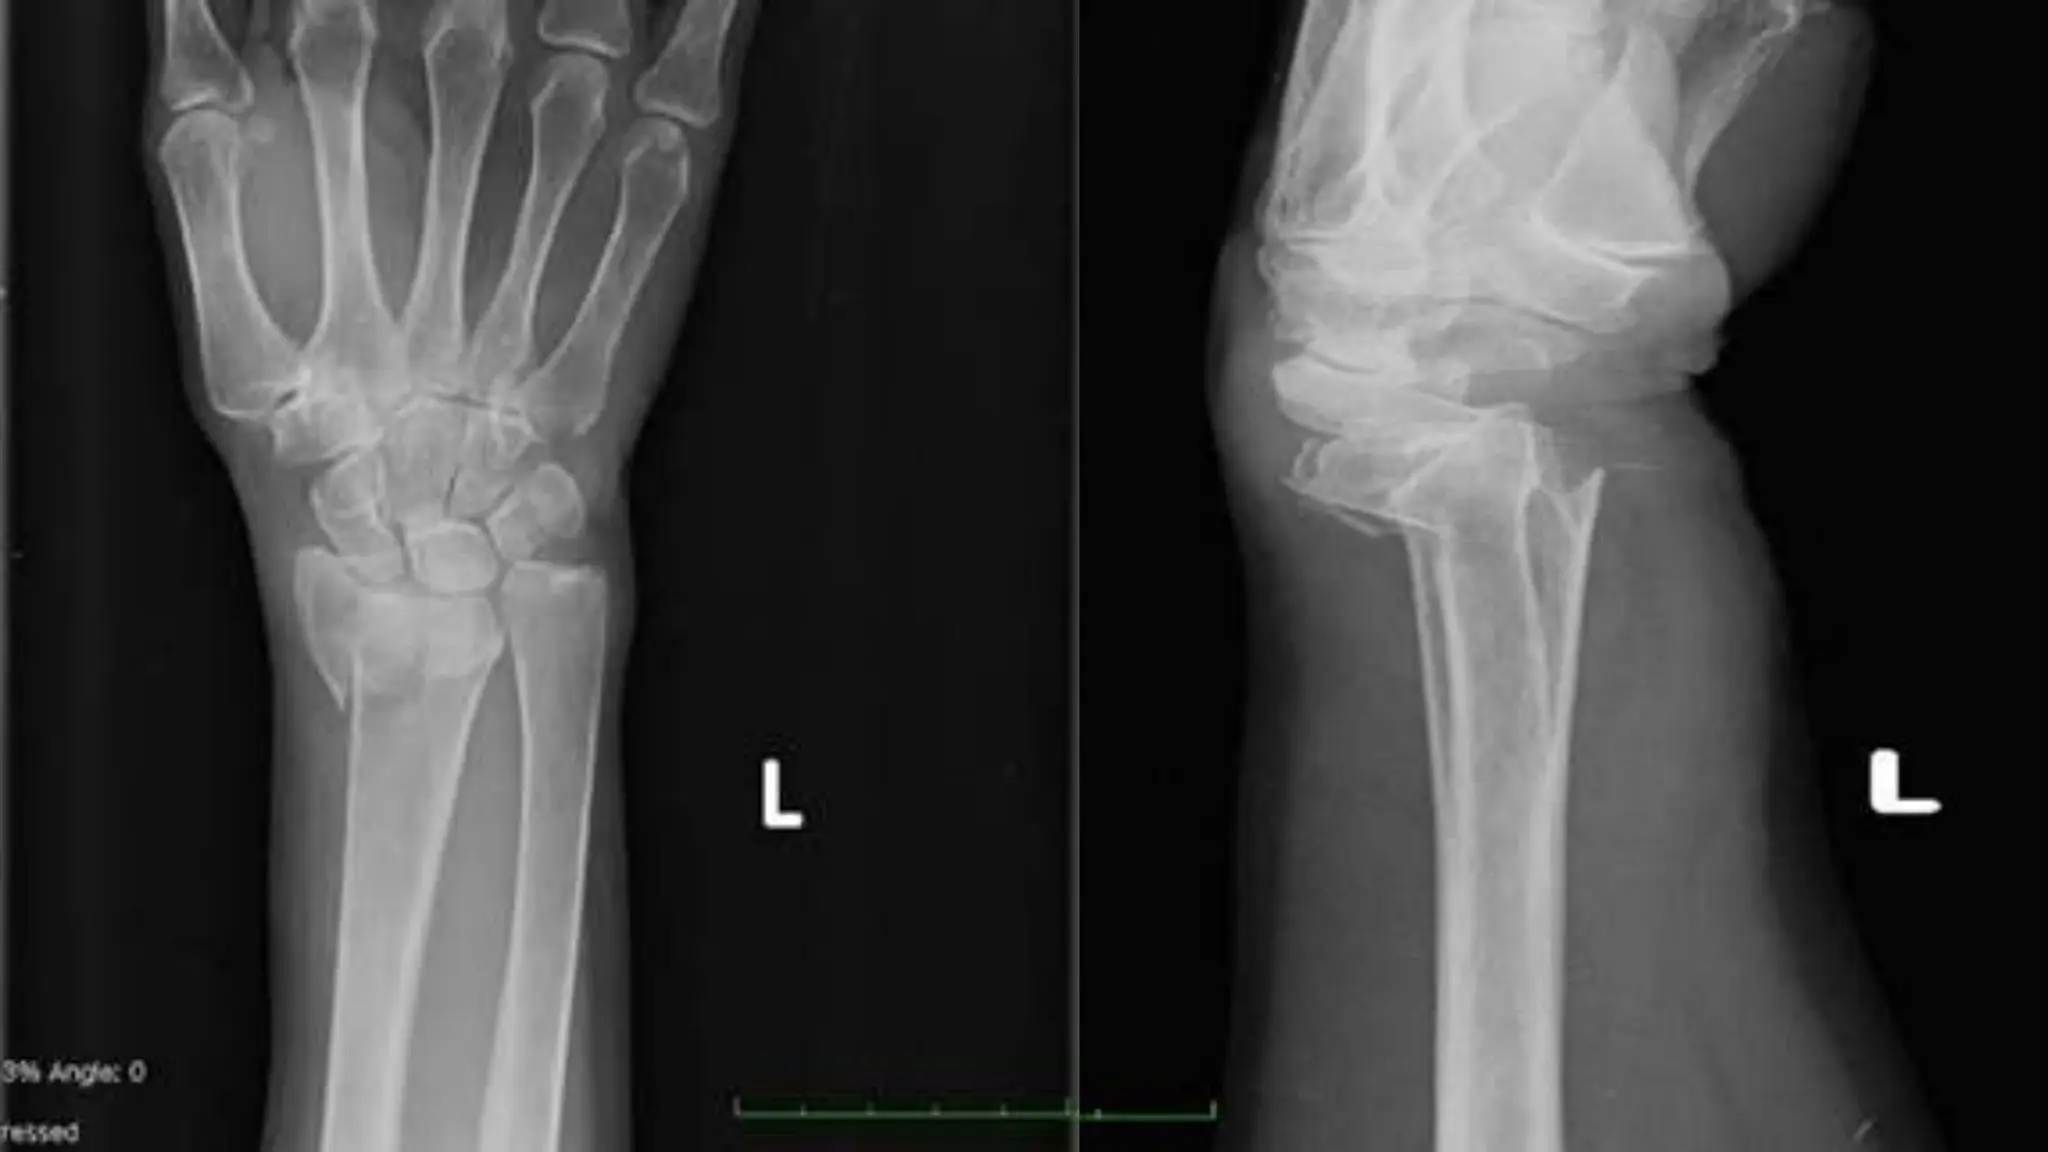

58 years old white woman presents to accident and emergency

department with left wrist pain, swelling, and displacement following a

fall onto outstretched hand at home.

X-ray: Colles’ fracture of distal radius present. Colles’ fracture

treated conservatively with cast and analgesia